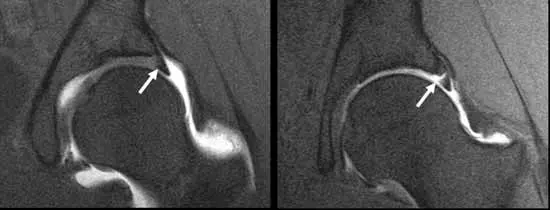

Diagnostic Approach

Labral tears are most effectively diagnosed using MRI arthrogram, which provides detailed imaging of labral tissue and surrounding structures. This enables surgeons to accurately assess tear patterns and plan surgical repair.